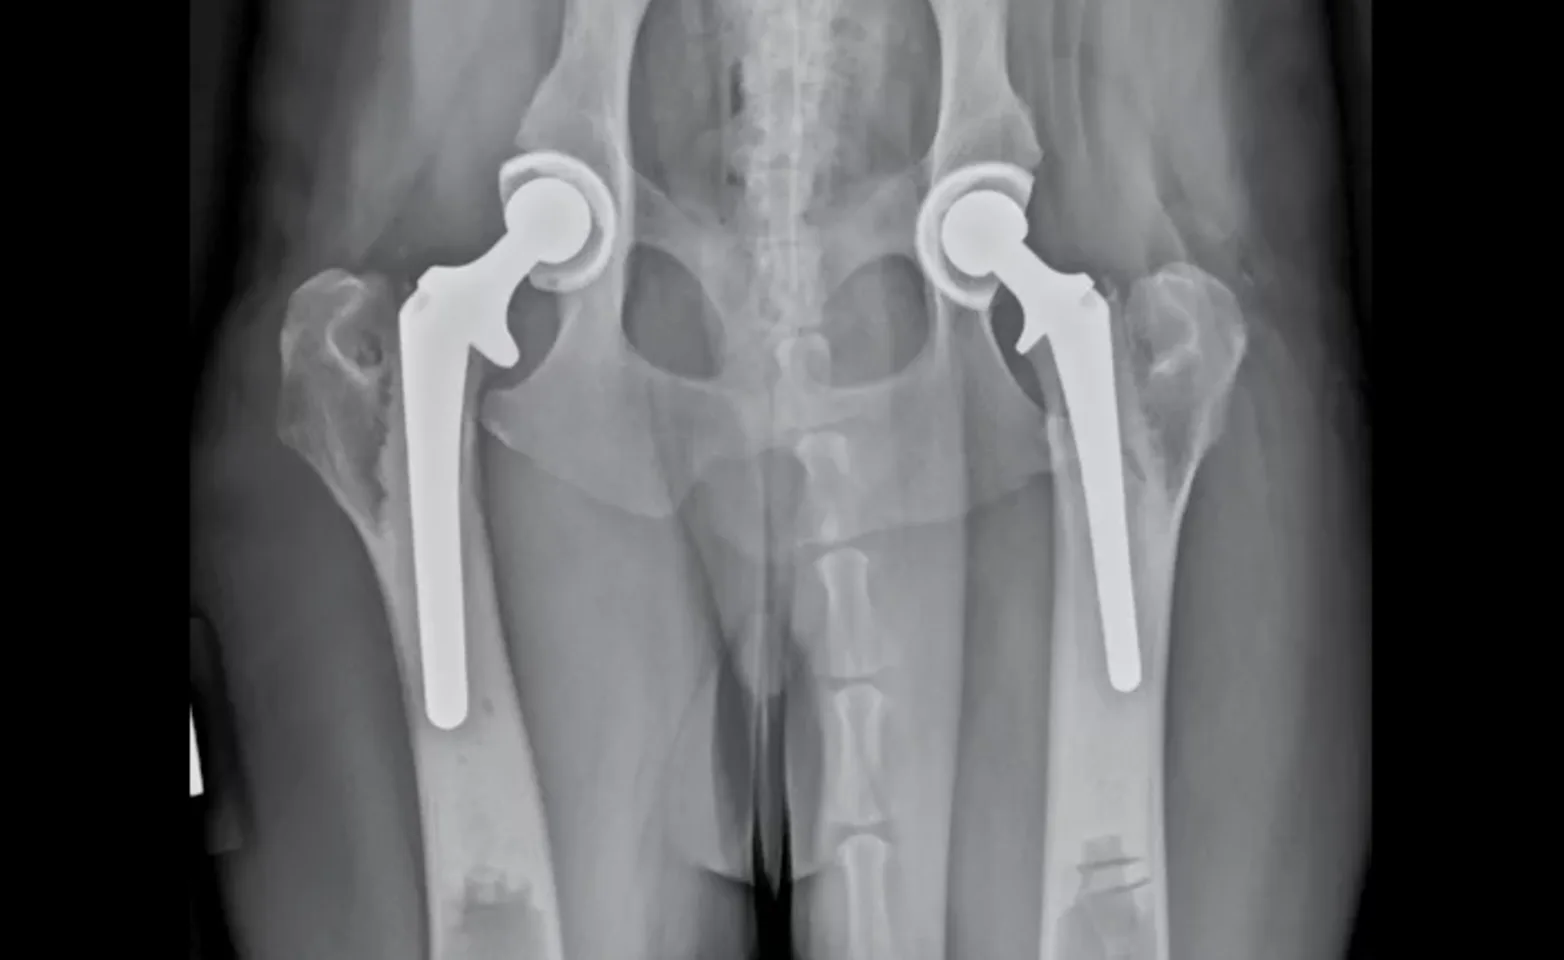

Total hip replacement (THR) is designed to eliminate the source of discomfort and restore range of motion by replacing the arthritic joint with an artificial hip joint prosthesis. The arthritic femoral head and neck are removed and replaced with a metal head and stem. The arthritic acetabulum is removed and replaced with a cup made of high-molecular-weight plastic. The metal head and plastic cup fit together like the original ball-and-socket joint, providing support and pain-free, mechanically-sound movement almost immediately after surgery.

The surgery can be performed on arthritic dogs over six months of age, but surgeons prefer to wait until 11 months of age or older when possible. Only one hip is operated on at a time, because it is difficult to facilitate an appropriate recovery if both hips are operated on simultaneously. Since dogs feel great after surgery and want to run as soon as they can, exercise restrictions must be enforced for three months following surgery to allow all the tissues around the prosthesis to heal. More than 97% of patients return to normal function after surgery. Pets can be expected to run, jump and play as they did before discomfort hindered them. THR typically lasts the lifetime of pets and offers the best long-term results.

Photo: This radiograph (x-ray) shows a hybrid total hip replacement.